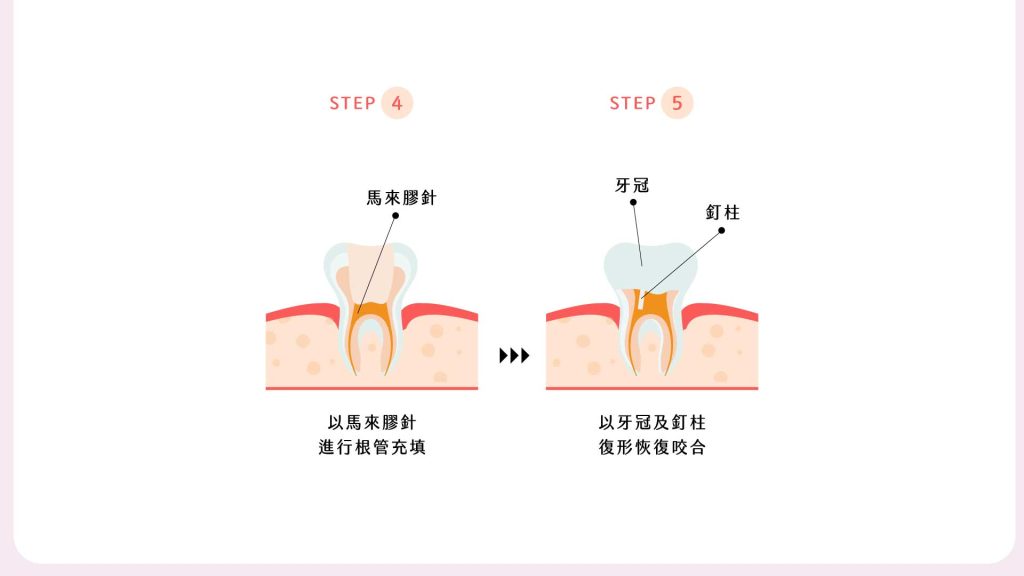

您可能沒聽過根管治療,但一定聽過「抽神經」,其實它們是相同的治療。當細菌感染牙齒內部的牙髓腔,健康神經失去活性,就需要將感染部位清理乾淨,再進行重建修復。

根管治療移除較多自然齒質,術後牙齒較脆弱,日後發生磨損、斷裂或崩壞的機率也增加,因此牙拜醫師建議使用牙套保護;另外根管治療屬於「內因性染色」,即色素沉積在牙齒內部,和「外因性染色」相反,因此無法透過外部美白來改善牙色,而同時能保護牙齒與美白的就是「全瓷冠」了。